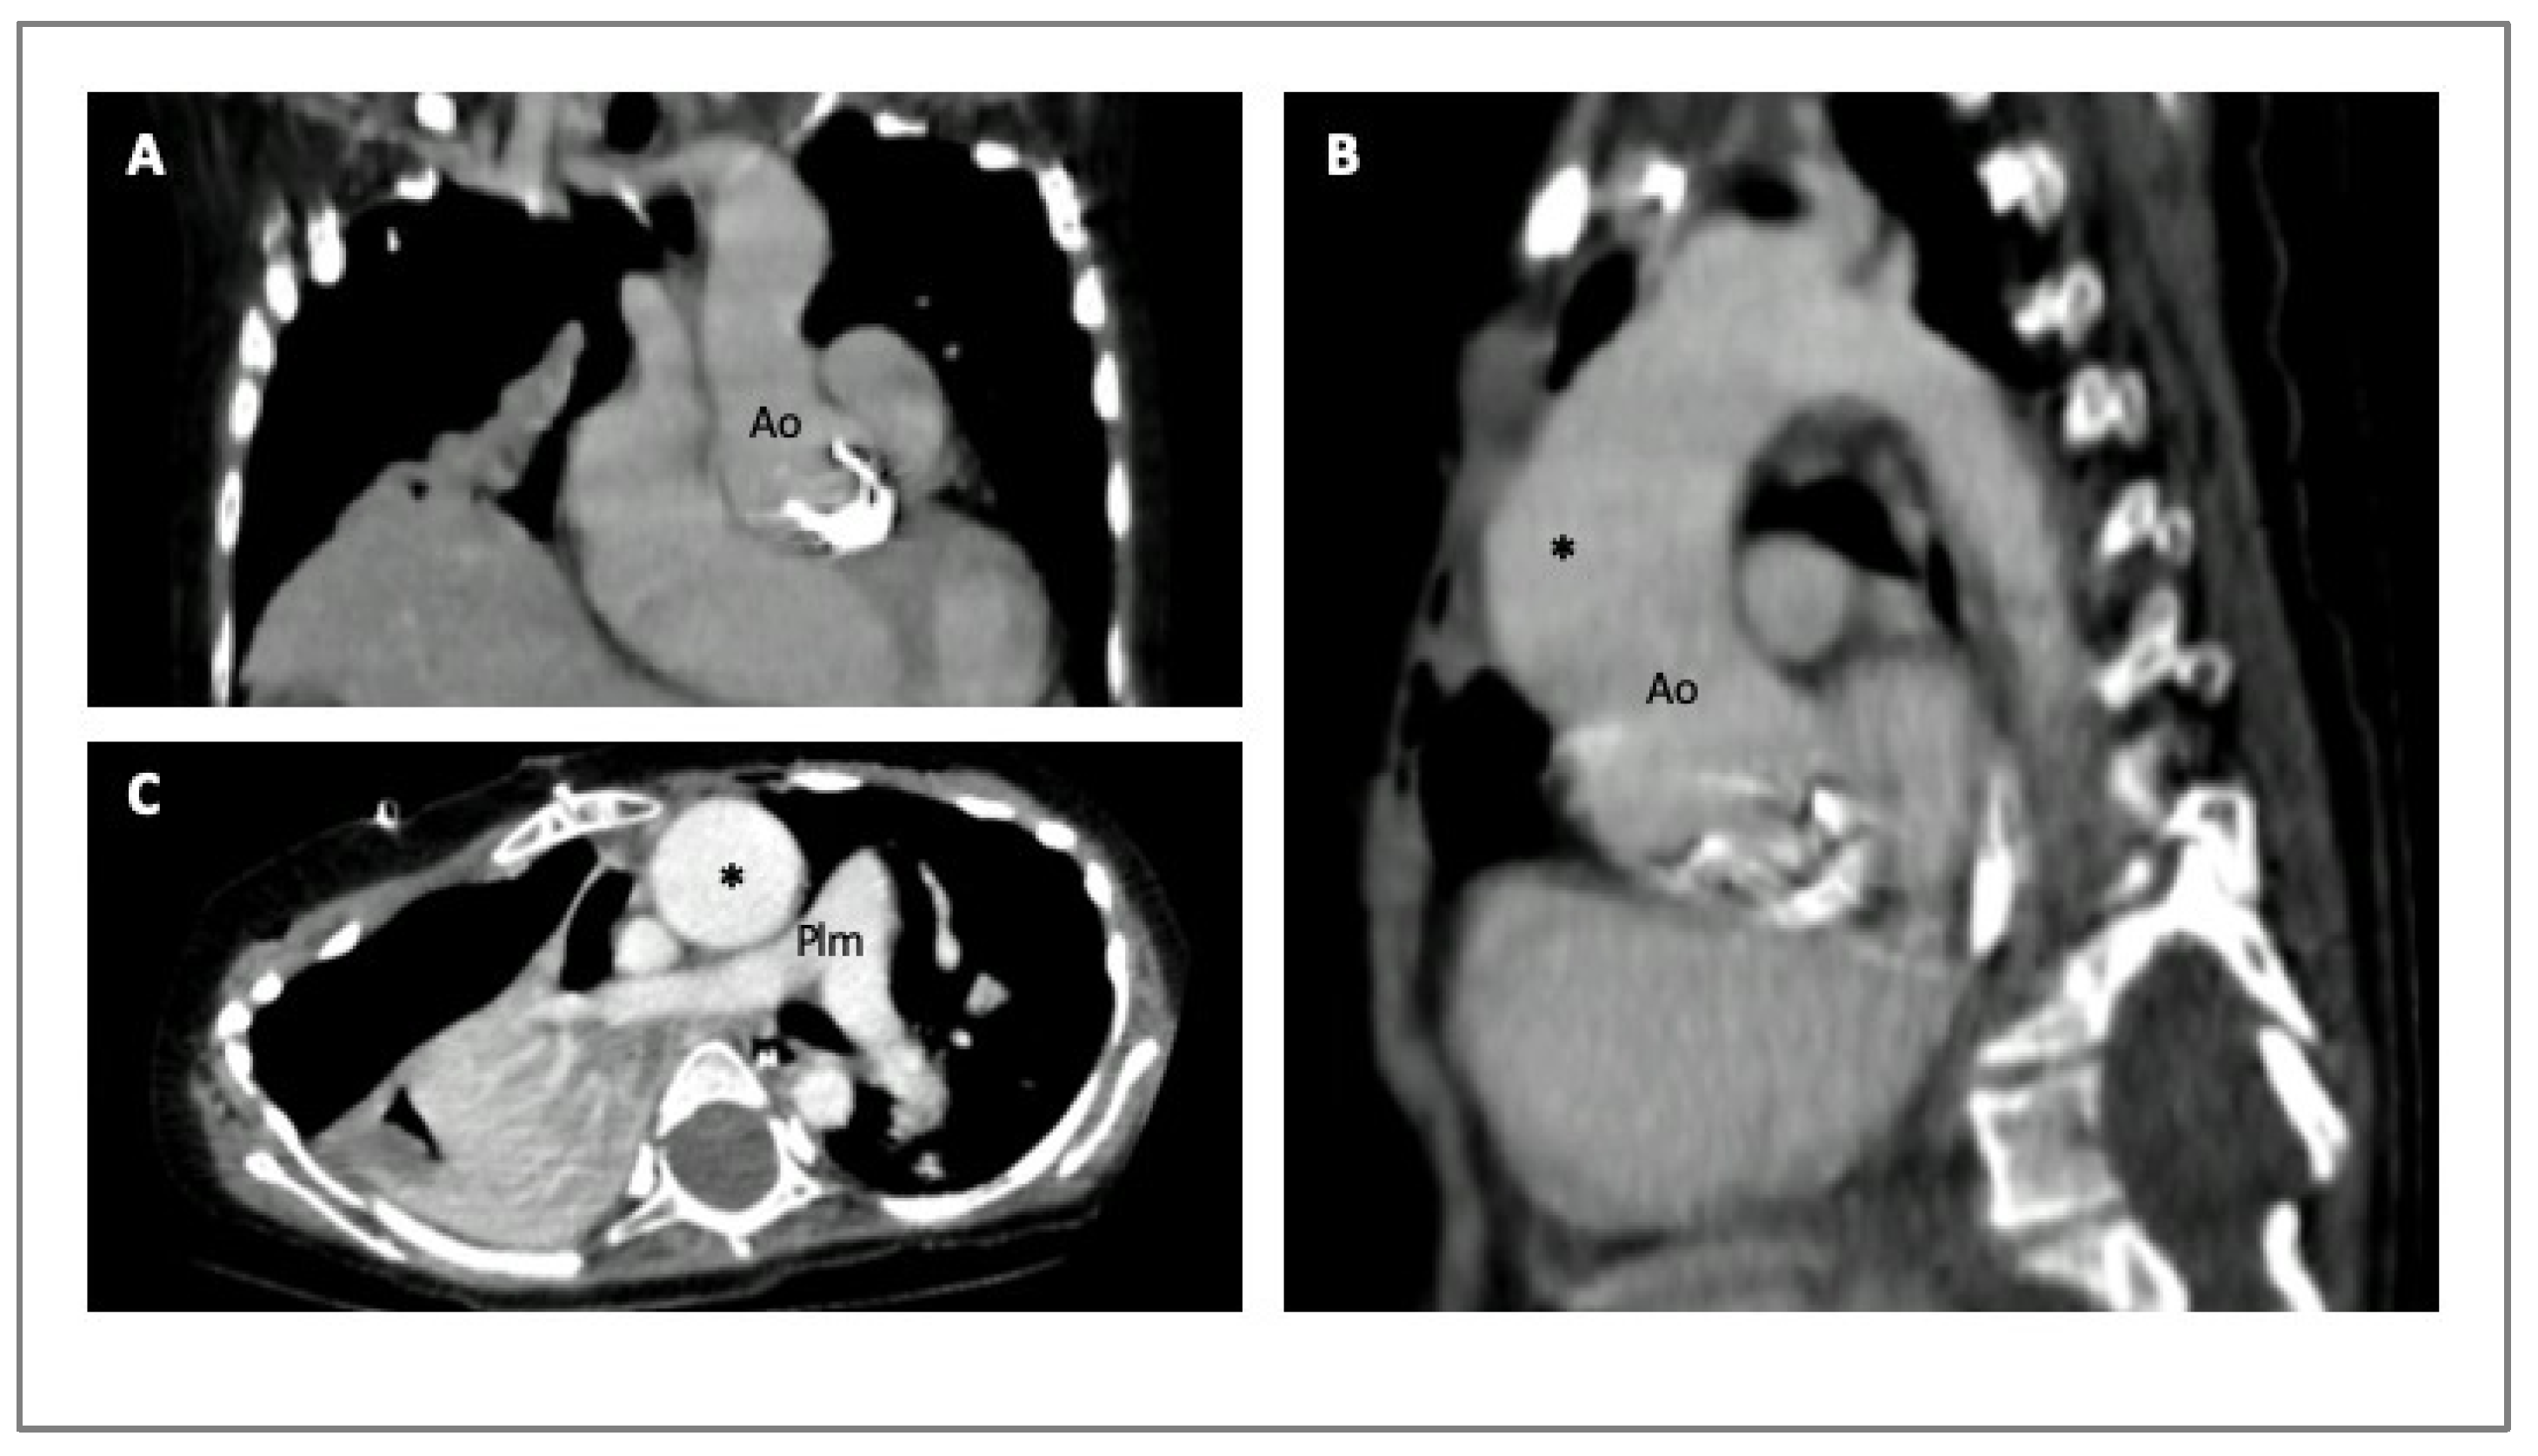

4. Imaging in HTADs

- Evangelista, A.; Sitges, M.; Jondeau, G.; Nijveldt, R.; Pepi, M.; Cuellar, H.; Pontone, G.; Bossone, E.; Groenink, M.; Dweck, M.R.; et al. Multimodality imaging in thoracic aortic diseases: A clinical consensus statement from the European Association of Cardiovascular Imaging and the European Society of Cardiology working group on aorta and peripheral vascular diseases. Eur. Heart J. Cardiovasc. Imaging 2023, 24, e65–e85. [Google Scholar] [CrossRef] [PubMed]

- Steinbrecher, K.L.; Marquis, K.M.; Braverman, A.C.; Ohman, J.W.; Bhalla, S.; Lin, C.Y.; Naeem, M.; Raptis, C.A. Imaging of Genetic Thoracic Aortopathy. Radiographics 2022, 42, 1283–1302. [Google Scholar] [CrossRef]